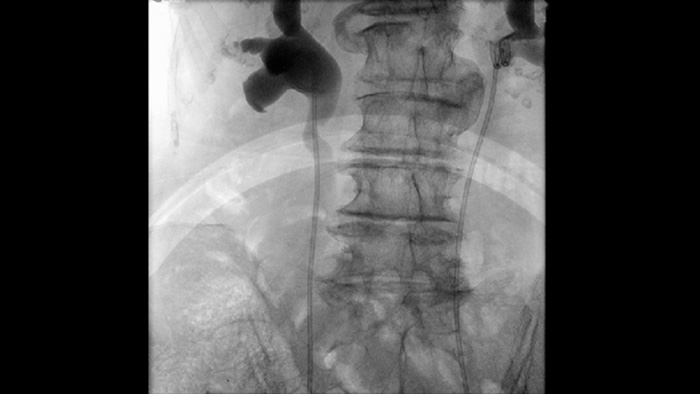

Fluoroscopia pulsada para obtener imágenes de las características anatómicas densas

La fluoroscopia pulsada mejora las imágenes de las características anatómicas densas y complejas para ayudarle en el manejo de la dosis. Puede seleccionar un rango de frecuencias de pulsos de fluoroscopia para reducir la dosis cuando se desee o mejorar la calidad de la imagen según sea necesario.